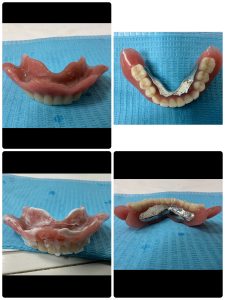

90歳メタルプレート装着3ヶ月チェックグッド👍